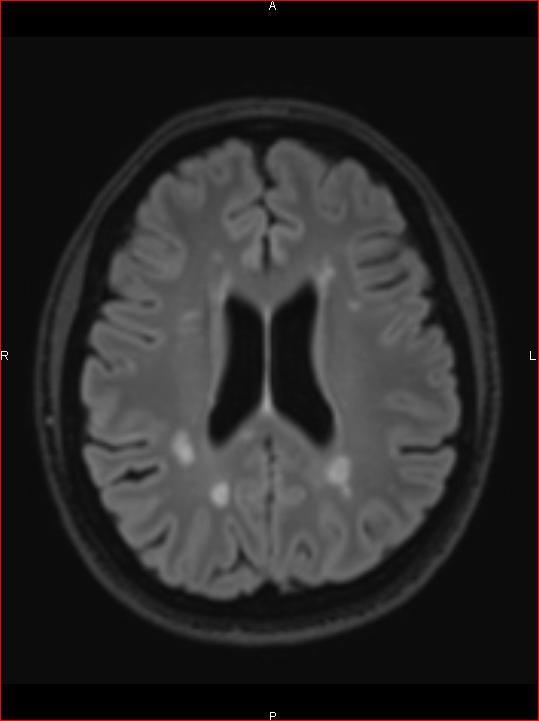

Lorsqu’il y a une atteinte du nerf optique, la motricité intrinsèque de l’œil concerné est intacte, alors que l’information lumineuse n’est pas relayée au cerveau, et donc n’active pas le réflexe photomoteur. C’est pour cela qu’il y a abolition des réflexes photomoteurs direct ipsilatéral et consensuel controlatéral à la lésion, mais conservation des réflexes photomoteurs consensuel ipsilatéral et direct controlatéral à la lésion.